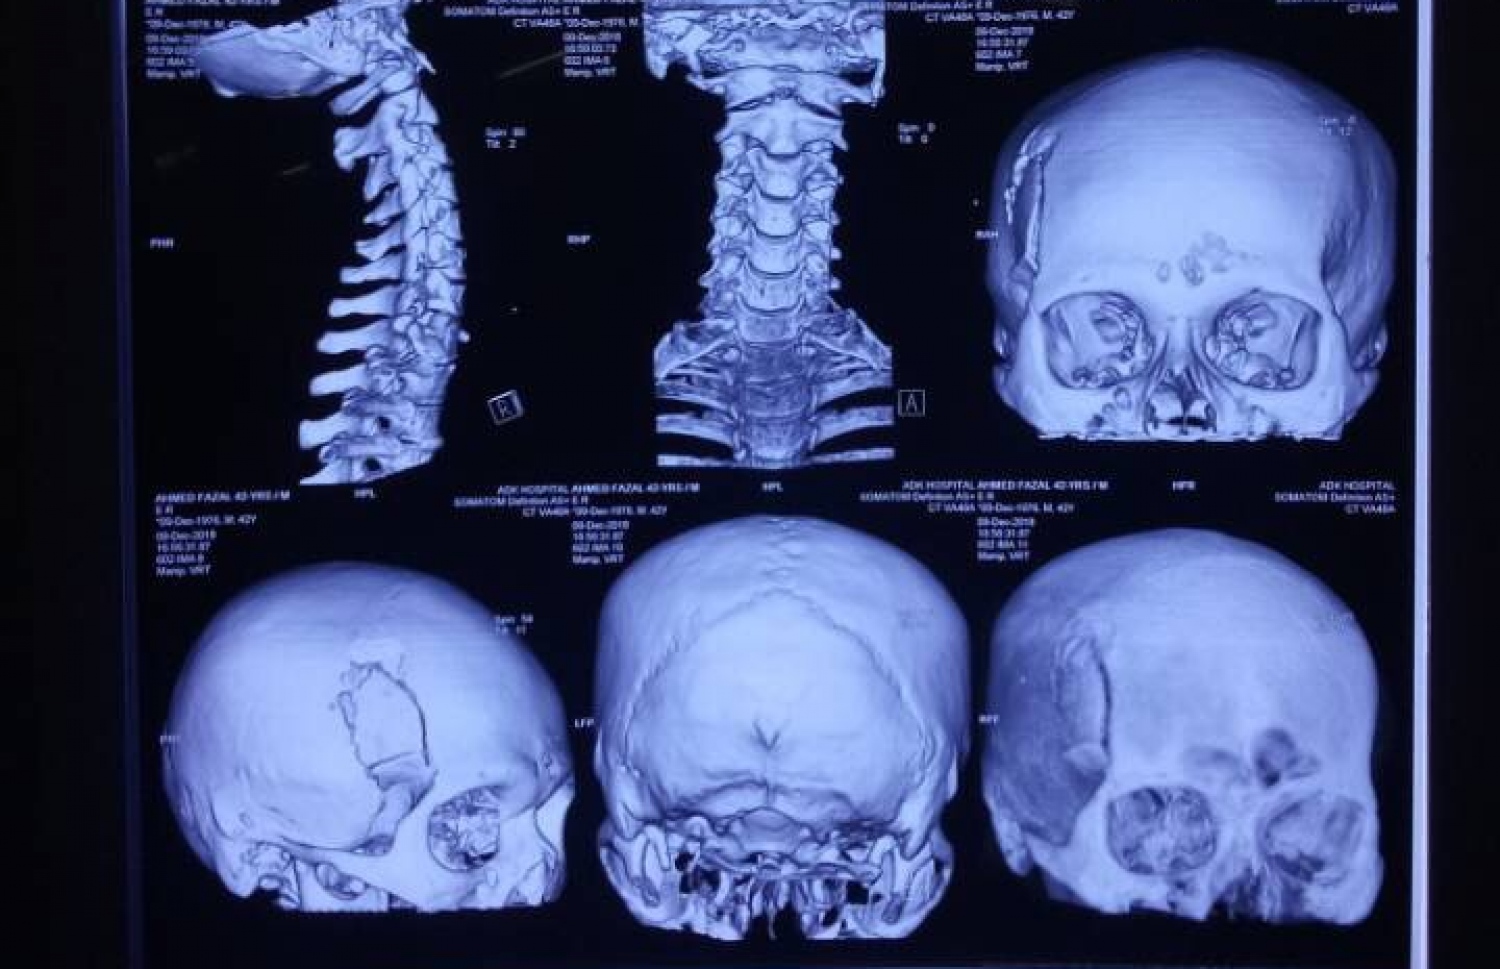

ބްރިޖުގައި އެކްސިޑެންޓުވި ފަޒާލްގެ ބޮލުގެ އެކްސްރޭއެއް: ބްރިޖުގައި ހިނގާ އެކްސިޑެންޓުތައް ގިނަ ކަމުން ކުއްލި ފިޔަވަޅުތަކެއް އެޅުމަށް ފުލުހުން ދަނީ މަސައްކަތް ކުރަމުން -- މިހާރު ފޮޓޯ

ތާރުގަނޑުގައި ޖެހުނުލެއް ބާރުކަމުން ފަޒާލްގެ ބޮލުގެ ވައަތު ފަޅީގެ ނާށިގަނޑު ފެޅި ސިކުނޑި އޮތީ ހާމައަށް ފެންނާށެވެ. ވައަތު އަތް ބިނދިފަ އެވެ.

ސިނަމާލެ ބްރިޖު ދިޔައީ ލެއިން ފޯވަމުންނެވެ. އޭނާ އޮތީ މަރުގެ ތުންފަތް މަތީގަ އެވެ. އެކަމަކު އޭނާ ވެއްޓުނީ އިންޑިއާގެ ދެ ޑޮކްޓަރުން ތިބި އެމްއެންޑީއެފްގެ ވެހިކަލެއްގެ ކުރިމައްޗަށެވެ. އެ ޑޮކްޓަރުން ވަގުތުން އޭނާއަށް ފަރުވާދޭން ފެށި އެވެ.